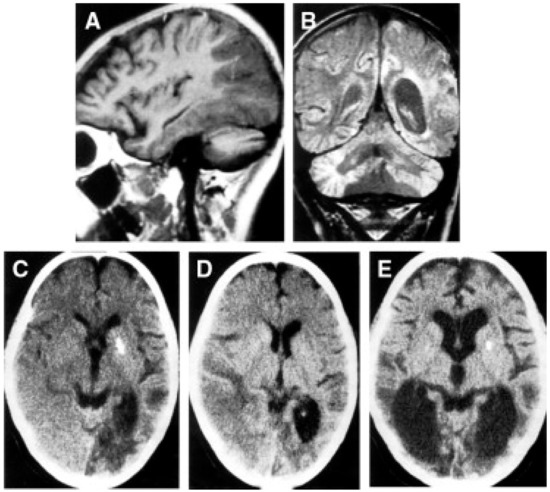

- Hirano, M.; Ricci, E.; Koenigsberger, M.R.; Defendini, R.; Pavlakis, S.G.; DeVivo, D.C.; DiMauro, S.; Rowland, L.P. Melas: An Original Case and Clinical Criteria for Diagnosis. Neuromuscul. Disord. 1992, 2, 125–135. [Google Scholar] [CrossRef]

- Savoiardo, M.; Bruzzone, M.G.; D’Incerti, L.; Farina, L.; Grisoli, M. Metabolic and Genetic Diseases of the Brain. Riv. Neuroradiol. 1999, 12, 73–86. [Google Scholar] [CrossRef]

- Mizukami, K.; Sasaki, M.; Suzuki, T.; Shiraishi, H.; Koizumi, J.; Ohkoshi, N.; Ogata, T.; Mori, N.; Ban, S.; Kosaka, K. Central Nervous System Changes in Mitochondrial Encephalomyopathy: Light and Electron Microscopic Study. Acta Neuropathol. 1992, 83, 449–452. [Google Scholar] [CrossRef]

- Tsuchiya, K.; Miyazaki, H.; Akabane, H.; Yamamoto, M.; Kondo, H.; Mizusawa, H.; Ikeda, K. MELAS with Prominent White Matter Gliosis and Atrophy of the Cerebellar Granular Layer: A Clinical, Genetic, and Pathological Study. Acta Neuropathol. 1999, 97, 520–524. [Google Scholar] [CrossRef]